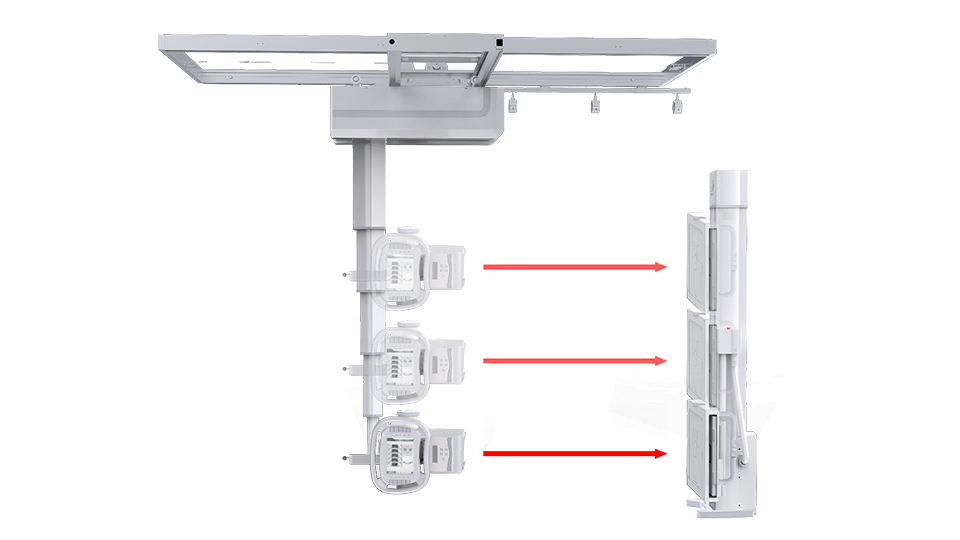

一機多用 PLD7600

一機多用 PLD7600

● 手動電動一體化

懸吊配備手動模式與電動模式,沿天軌橫縱移動時可選手動或電動,滿足不同醫護人員使用習慣。